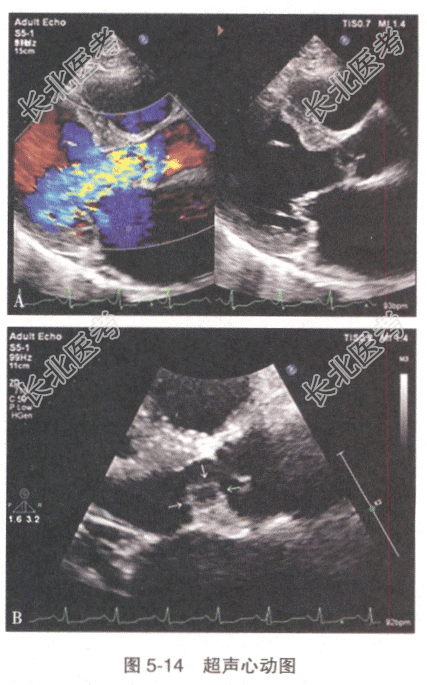

患者,男性,41岁。因“发热、头痛,胸闷1周,进行性加重6小时”入院,平素身体健康,1周前拔牙后发热至39.5℃,口服抗生素症状缓解。查体:T38.7℃,P117次/min,R24次/min,BP132/85mmHg;血常规提示WBC15.4×10⁹/L,N85%;心脏彩超检查见图5-14:主动脉瓣叶增厚、毛糙,瓣叶可见多个强回声团附着,左冠瓣体可见一囊袋样结构,其上可见数个连续中断。